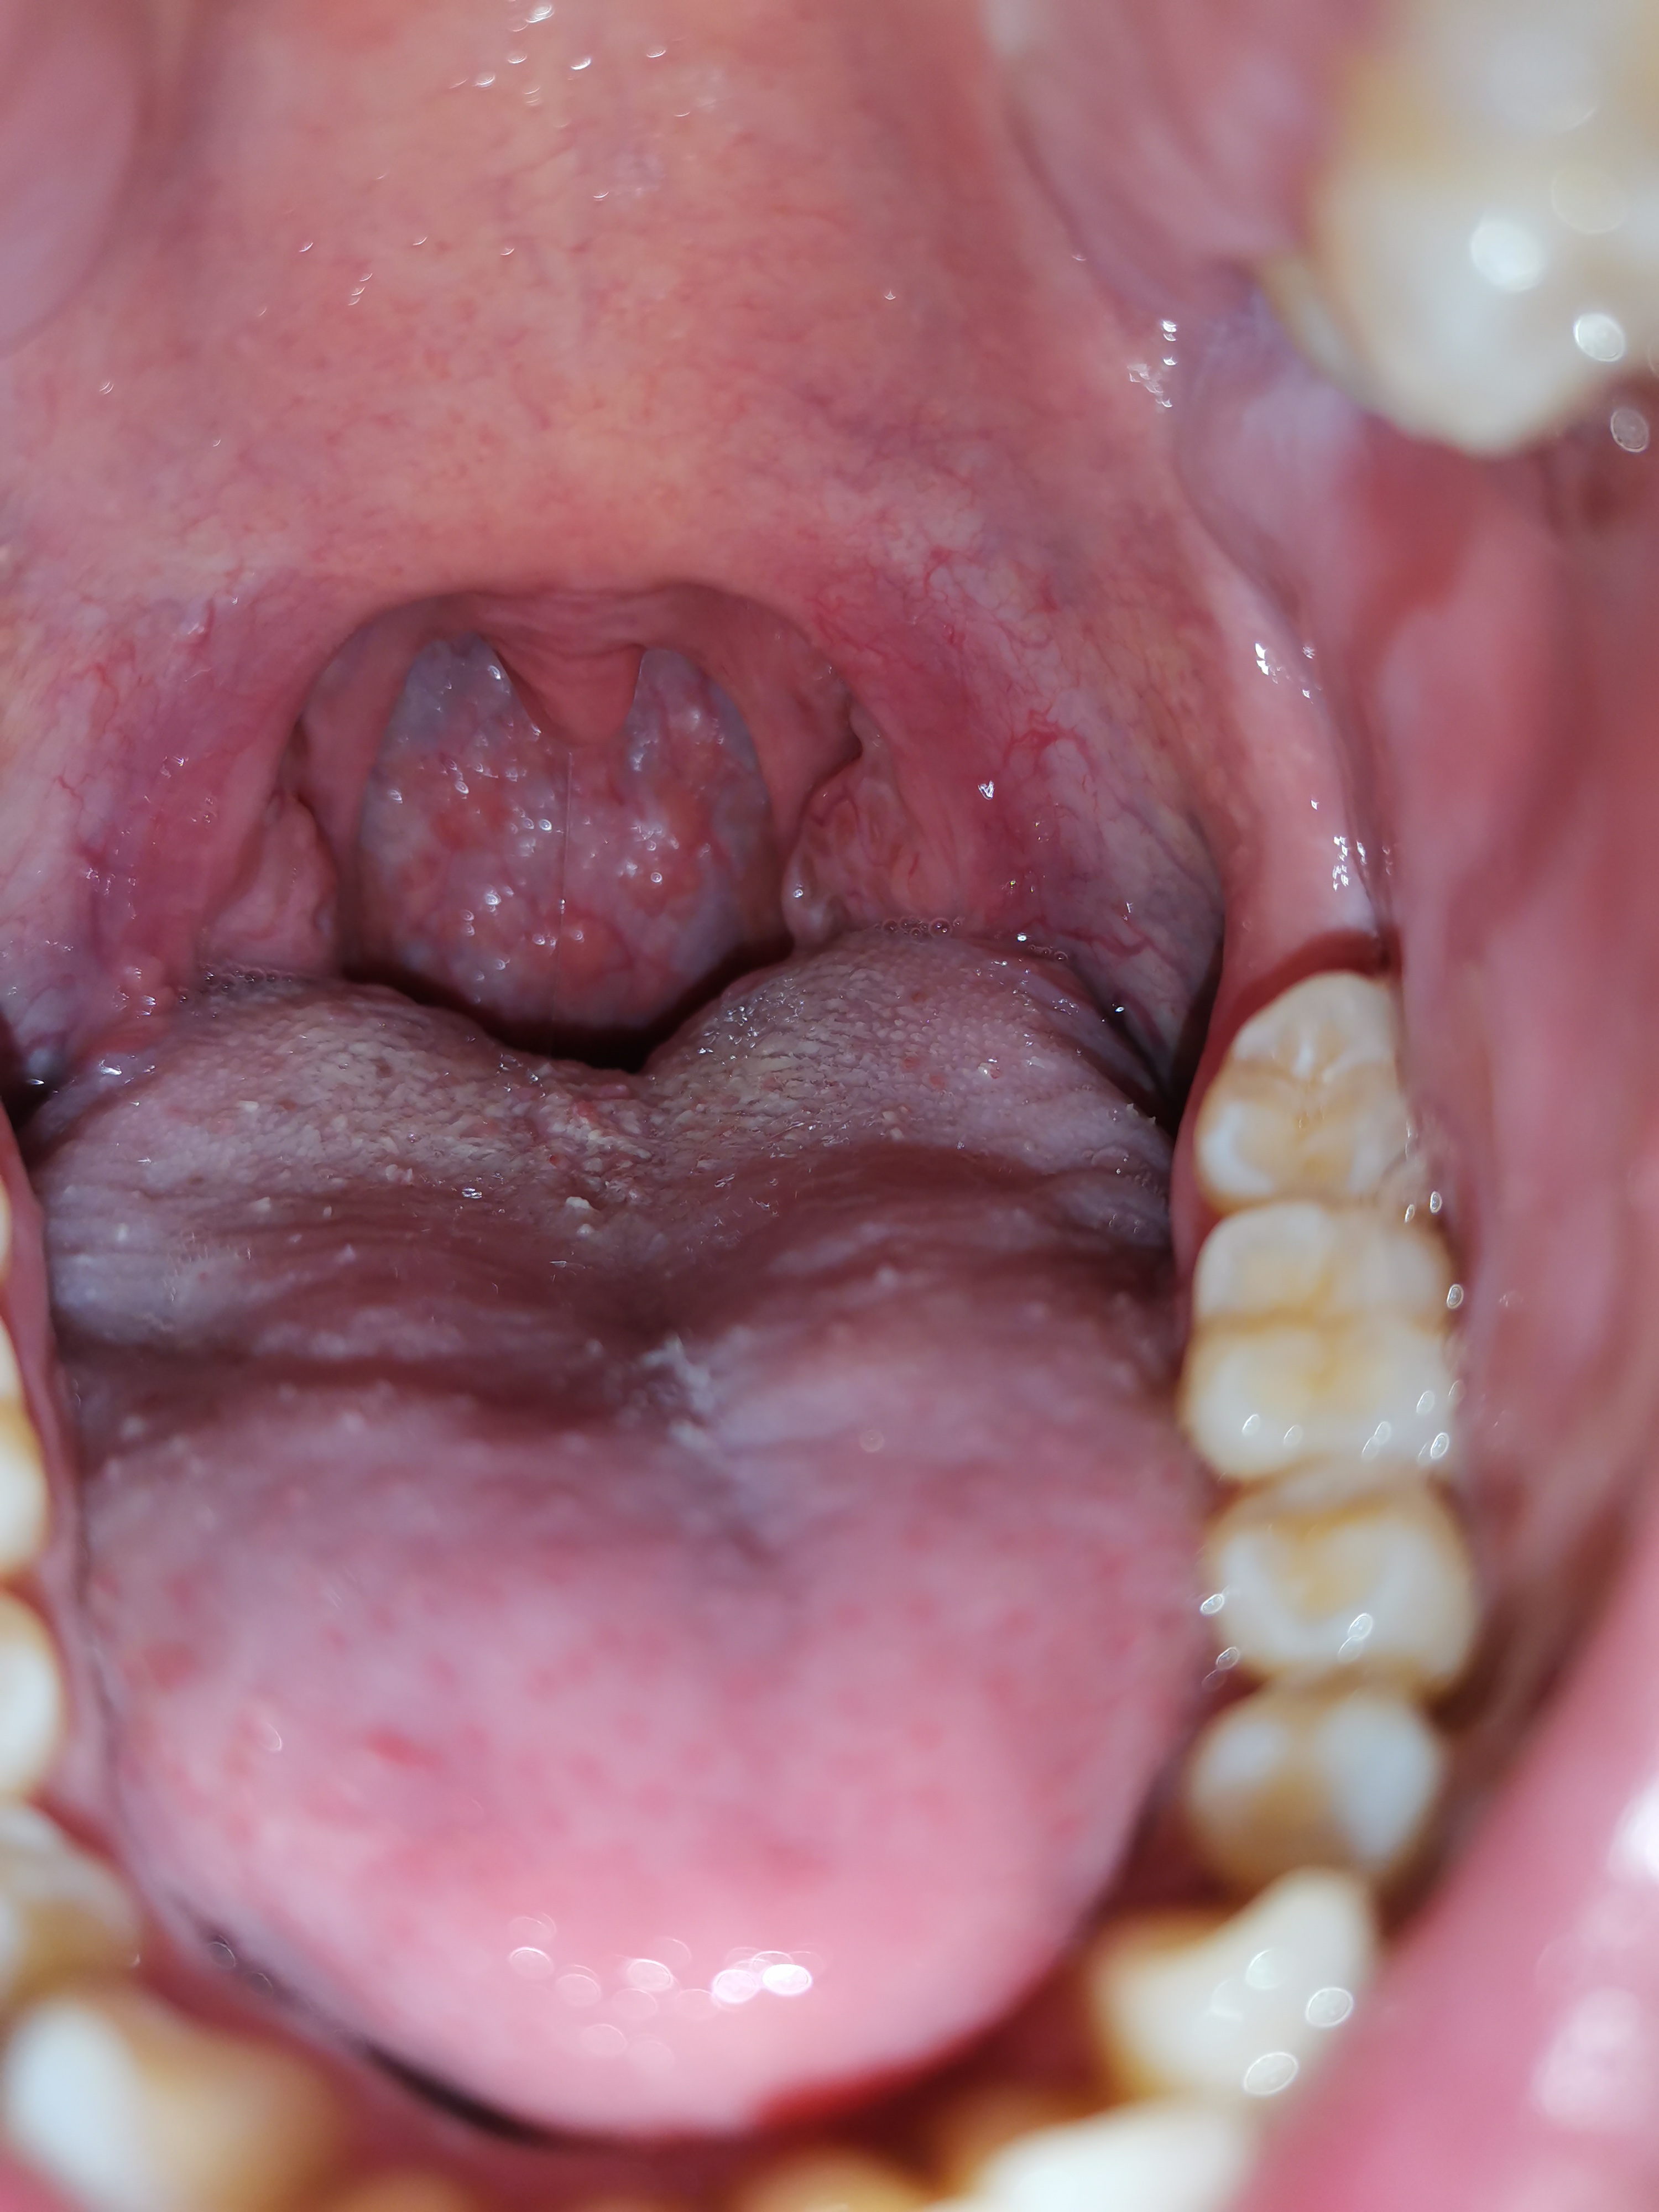

Ulcera sul palato

Buonasera Vi scrivo perché inizio a preoccuparmi un po per un'ulcera sul palato della bocca. È dolorosa e da circa una settimana mi da noie anche quando mangio. Ho preso appuntamento con il mio dentista di fiducia ma a causa covid devo aspettare altre due settimane. Questa cosa è comparsa dalla notte al giorno...e

Leggi tutto